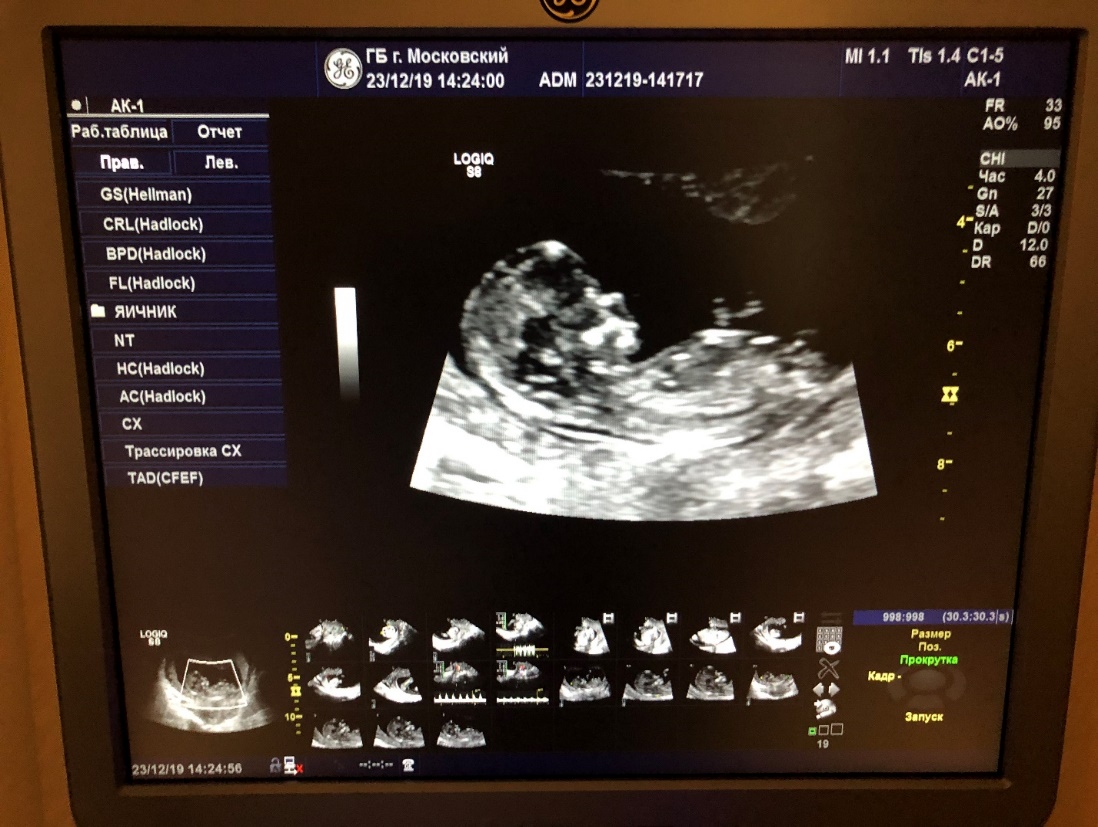

Я так думала, потому что токсикоз и общее состояние было очень схоже с тем, когда я носила дочку. Ко всему прочему, я стала вязать, да еще и яркий розовый шарф, розовый плед из крупной плюшевой пряжи, красить ногти в золотой цвет, короче, как я еще не накупила красных платьев и ярких колясок. Мы всей семьёй сразу же единогласно решили, что у нас будет Алёнка. Но в один прекрасный вечер, перед очередным УЗИ, Алёнка стала давать мне под рёбра. Я прям боялась этих ударов… Уж очень агрессивно. А на следующий день мне сказали, что у нас стопроцентный мальчик… Я была слегка шокирована. Хорошо, что старшая дочь была со мной на этом УЗИ. Мы шли молча. Муж пришёл поздно вечером и тоже не мог поверить услышанному. Ну, ничего, всю ночь я гладила живот и разговаривала с сыном. Больше он не бил в рёбра и вёл себя спокойно. Мне пришло имя для него в этот вечер -Лев. Так и назвали. Можно, конечно, сдать на ранних сроках тест генетический и сразу узнать пол, но сегодня это дорогое удовольствие. Поэтому проще не придавать сильное значение полу, а любить своего малыша без условностей.